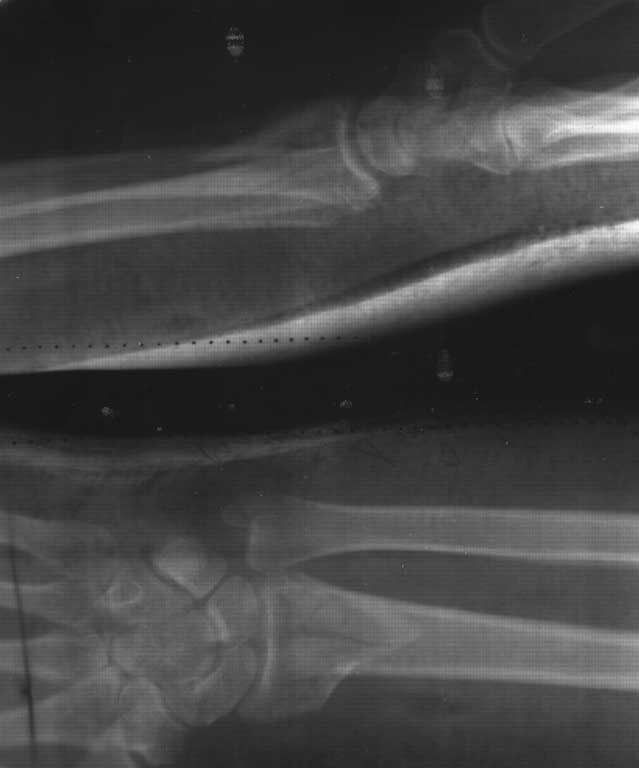

Имеется пациентка Ч. 42 лет. 20 мая 2012 года- перелом метаепифиза левой лучевой кости, со смещением отломков. После репозиции стояние отломков удовлетворительное. 10 июня 2012 - Р-контроль, имеется смещение отломков (снимки прилагаются).

Нарушены все три критерия репозици внесуставных переломов дистального луча:

1. Есть укорочение (лучевая кость короче локтевой).

2. Суставная поверхность развернута к тылу ( а должна быть к ладони).

3. Уменьшен угол наклона в локтевую сторону.

Прошу прощения, сразу не разглядел, нарушены два критерия. Наклон суставной поверхности к ладони сохранен. Но тем не менее более важным параметром является восстановление длины лучевой кости.

По снимку я оцениваю , что резко уменьшен радиоульнарный угол, и радиальное удилинение отсутствует( около -10 мм). А это говорит об укорочении. Я правильно думаю?

Вы имеете ввиду наверное радио-ульнарный индекс. Но судить о его изменении можно только имея на руках снимок здоровой руки. Визуально, судя по снимкам, из деформации осталась лучевая дивиация. При подобной рентген-картине после адекватного восстановительного лечения можно добиться практически полной функции, но при активном образе жизни эта деформация приведет к более быстрому развитию деформирующего артроза кистевого сустава, наиболее выраженного со стороны локтевой кости.